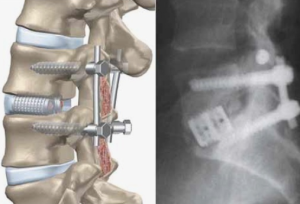

Для достижения и восстановления сагиттального баланса у этого пациента мы решили провести хирургическое планирование с остеотомией Понте на поясничном отделе и выполнить заднюю фиксацию. Цели этой операции — декомпрессия нервных элементов, выравнивание позвоночника во фронтальной и сагиттальной плоскостях и минимизация периоперационных осложнений. В качестве хирургических задач мы использовали несколько целевых параметров: SVA <25°, несоответствие PI LL <10° и LL 20°-45° [5]. Пациент находился в положении лежа на животе с подушкой. Был выполнен линейный разрез с субпериостальной диссекцией для обнажения T10—S1. Затем на T10 и T11 были установлены монолитные винты 40 мм, а на T12 — полимерные винты 40 мм с использованием экстрапедикулярной техники. Также были установлены другие винты 40 мм на L1, L3 и L5; и полимерные винты 35 мм на S1. Остеотомии по Понте были выполнены на уровне L1- L4 до момента мобилизации. Затем они были зафиксированы с помощью стержневых винтов и гаек. Кровотечение контролировалось биполярным катетером, хирургическим клеем и костным воском. После сращения костей был установлен эпидуральный катетер для введения анальгетиков. Процедура проводилась послойным наложением швов. После операции пациент был переведен в отделение интенсивной терапии на 3 дня, а затем в промежуточную палату. Послеоперацион - ное рентгеновское исследование показало, что SVA составило 43 мм, что соответствует целевому значению. Угол LL составил 25° (норма), а угол PI минус LL — 20°. Пациент был выписан через 7 дней после операции, и было запланировано плановое наблюдение и осмотр в амбулаторной и реабилитационной клинике. На 3-м месяце наблюдения осанка пациента улучшилась до такой степени, что он мог видеть лицо другого человека во время разговора, при этом сохранялась минимальная боль. Однако для улучшения осанки пациенту по-прежнему необходимо стоять на цыпочках левой ноги. Для публикации данного клинического случая было получено информированное согласие пациента.

Наша цель — упростить процедуру, сделав ее одноэтапной, чтобы уменьшить вероятность хирургических осложнений. Остеотомия Понте позволяет корректировать кифоз с чисто заднего доступа. Остеотомия Понте включает удаление определенных частей структуры позвоночника, таких как кости и связки, для коррекции деформаций. На каждом уровне остеотомии обычно достигается коррекция в диапазоне 5°-10°. Важно удалить желтую связку, чтобы избежать ее давления на нервы или спинной мозг при закрытии остеотомии [11, 12]. У нашего пациента была выполнена многоуровневая остеотомия Понте на уровнях L1- L4 для достижения нормального угла пояснично-латерального отдела позвоночника. Мы планировали выполнить многоуровневую остеотомию с целью коррекции угла пояснично-латерального отдела позвоночника примерно на 30°. После операции мы заметили, что сагиттальная вертикальная ось (СВА) и пояснично-латеральный отдел позвоночника вернулись в нормальное положение. Однако наблюдалось увеличение PI, и разница между PI и LL, известная как несоответствие PI и LL, по-прежнему превышала 10°. Эти послеоперационные изменения могут быть результатом хирургического вмешательства. Предыдущее исследование Меррилла и др. предполагает, что хирургическая коррекция может влиять на различные сегменты позвоночника и таза.[13] Ли и др. также сообщили об увеличении PI у всех пациентов, перенесших хирургическую коррекцию сагиттальных деформаций у взрослых. Это изменение PI может происходить в ответ на увеличение силы сдвига в крестцово-подвздошном суставе, что может произойти после хирургической коррекции фиксированного LL [14].